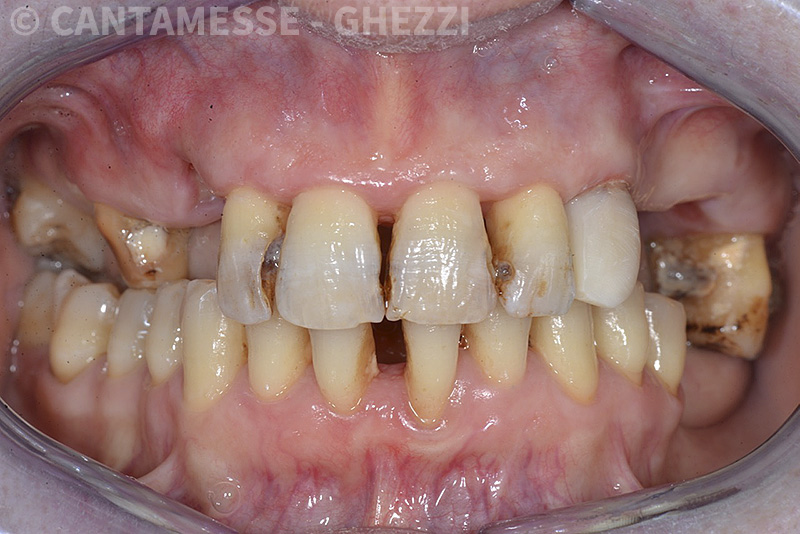

PREMESSA: in seguito all’estrazione dell’incisivo laterale superiore di destra, resasi necessaria per cause batteriche, si decide di affrontare il caso con il posizionamento di un impianto in sostituzione dell’elemento mancante dopo guarigione del sito infetto. Con tecniche rigenerative sia dei tessuti ossei mancanti a causa dell’infezione pregressa, sia dei tessuti gengivali che appaiono inizialmente troppo spostati in alto, si ripristina una corretta morfologia delle parabole (contorni) gengivali e delle papille interdentali (triangoli di gengiva tra due denti vicini).